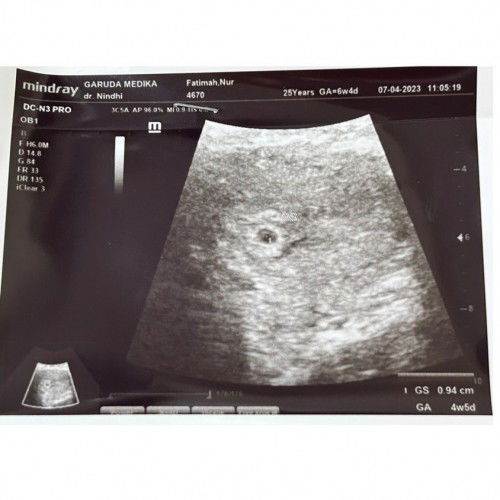

Hpht 20 feb

Hpht 20 feb kalo dihitung 6w4d, ngeberaniin buat usg Alhamdulillah kantong kehamilan udah terlihat meskipun sangat mungil tertulis 4w5d. Kontrol lagi dibulan depan. Semoga berkembang dan diberi sehat selalu, Aamiin ya Rabb. 🙏🏻